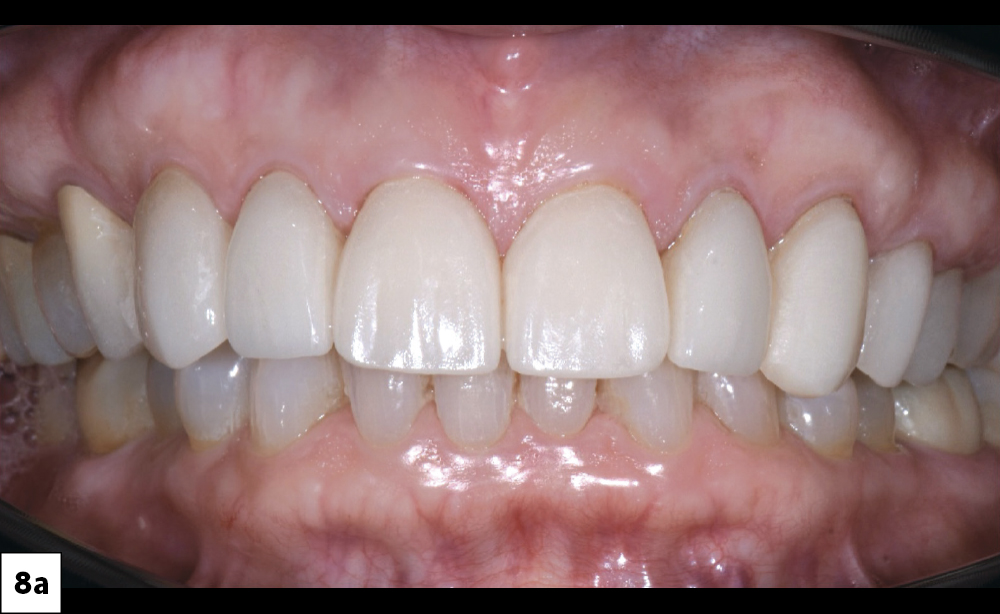

he gingivectomy on #8 & #9 resulted in gingival symmetry

The restorations were seated with Variolink® Esthetic resin cement (Ivoclar Vivadent)

Figures 8a, 8b: The gingivectomy on #8 & #9 resulted in gingival symmetry. The restorations were seated with Variolink® Esthetic resin cement (Ivoclar Vivadent). After tack-curing to facilitate cleanup, I removed excess cement and completed light curing from all aspects to ensure full polymerization. This sequence produced a durable and predictable bond while preserving the customized esthetic characterization of the Obsidian restorations.